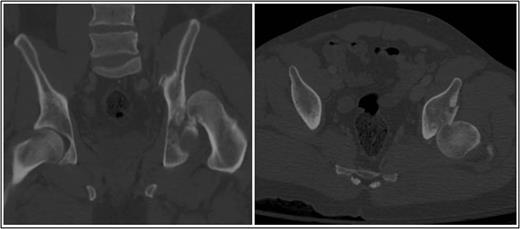

Coronal and axial CT pelvis of the left femoral head engaging with the postero-superior acetabulum.